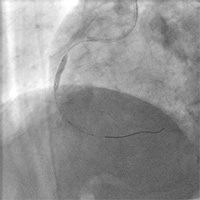

細くなったところが見つかれば、そこにバルーンやステントをおいて血管を広げていきます。

細くなったところが見つかれば、そこにバルーンやステントをおいて血管を広げていきます。

右冠動脈が詰まりかけています

ステントで広げて…

流れるようになりました